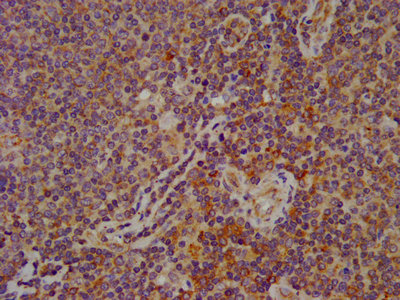

IHC image of CSB-PA008279LA01HU diluted at 1:600 and staining in paraffin-embedded human lymph node tissue performed on a Leica BondTM system. After dewaxing and hydration, antigen retrieval was mediated by high pressure in a citrate buffer (pH 6.0). Section was blocked with 10% normal goat serum 30min at RT. Then primary antibody (1% BSA) was incubated at 4°C overnight. The primary is detected by a biotinylated secondary antibody and visualized using an HRP conjugated SP system.